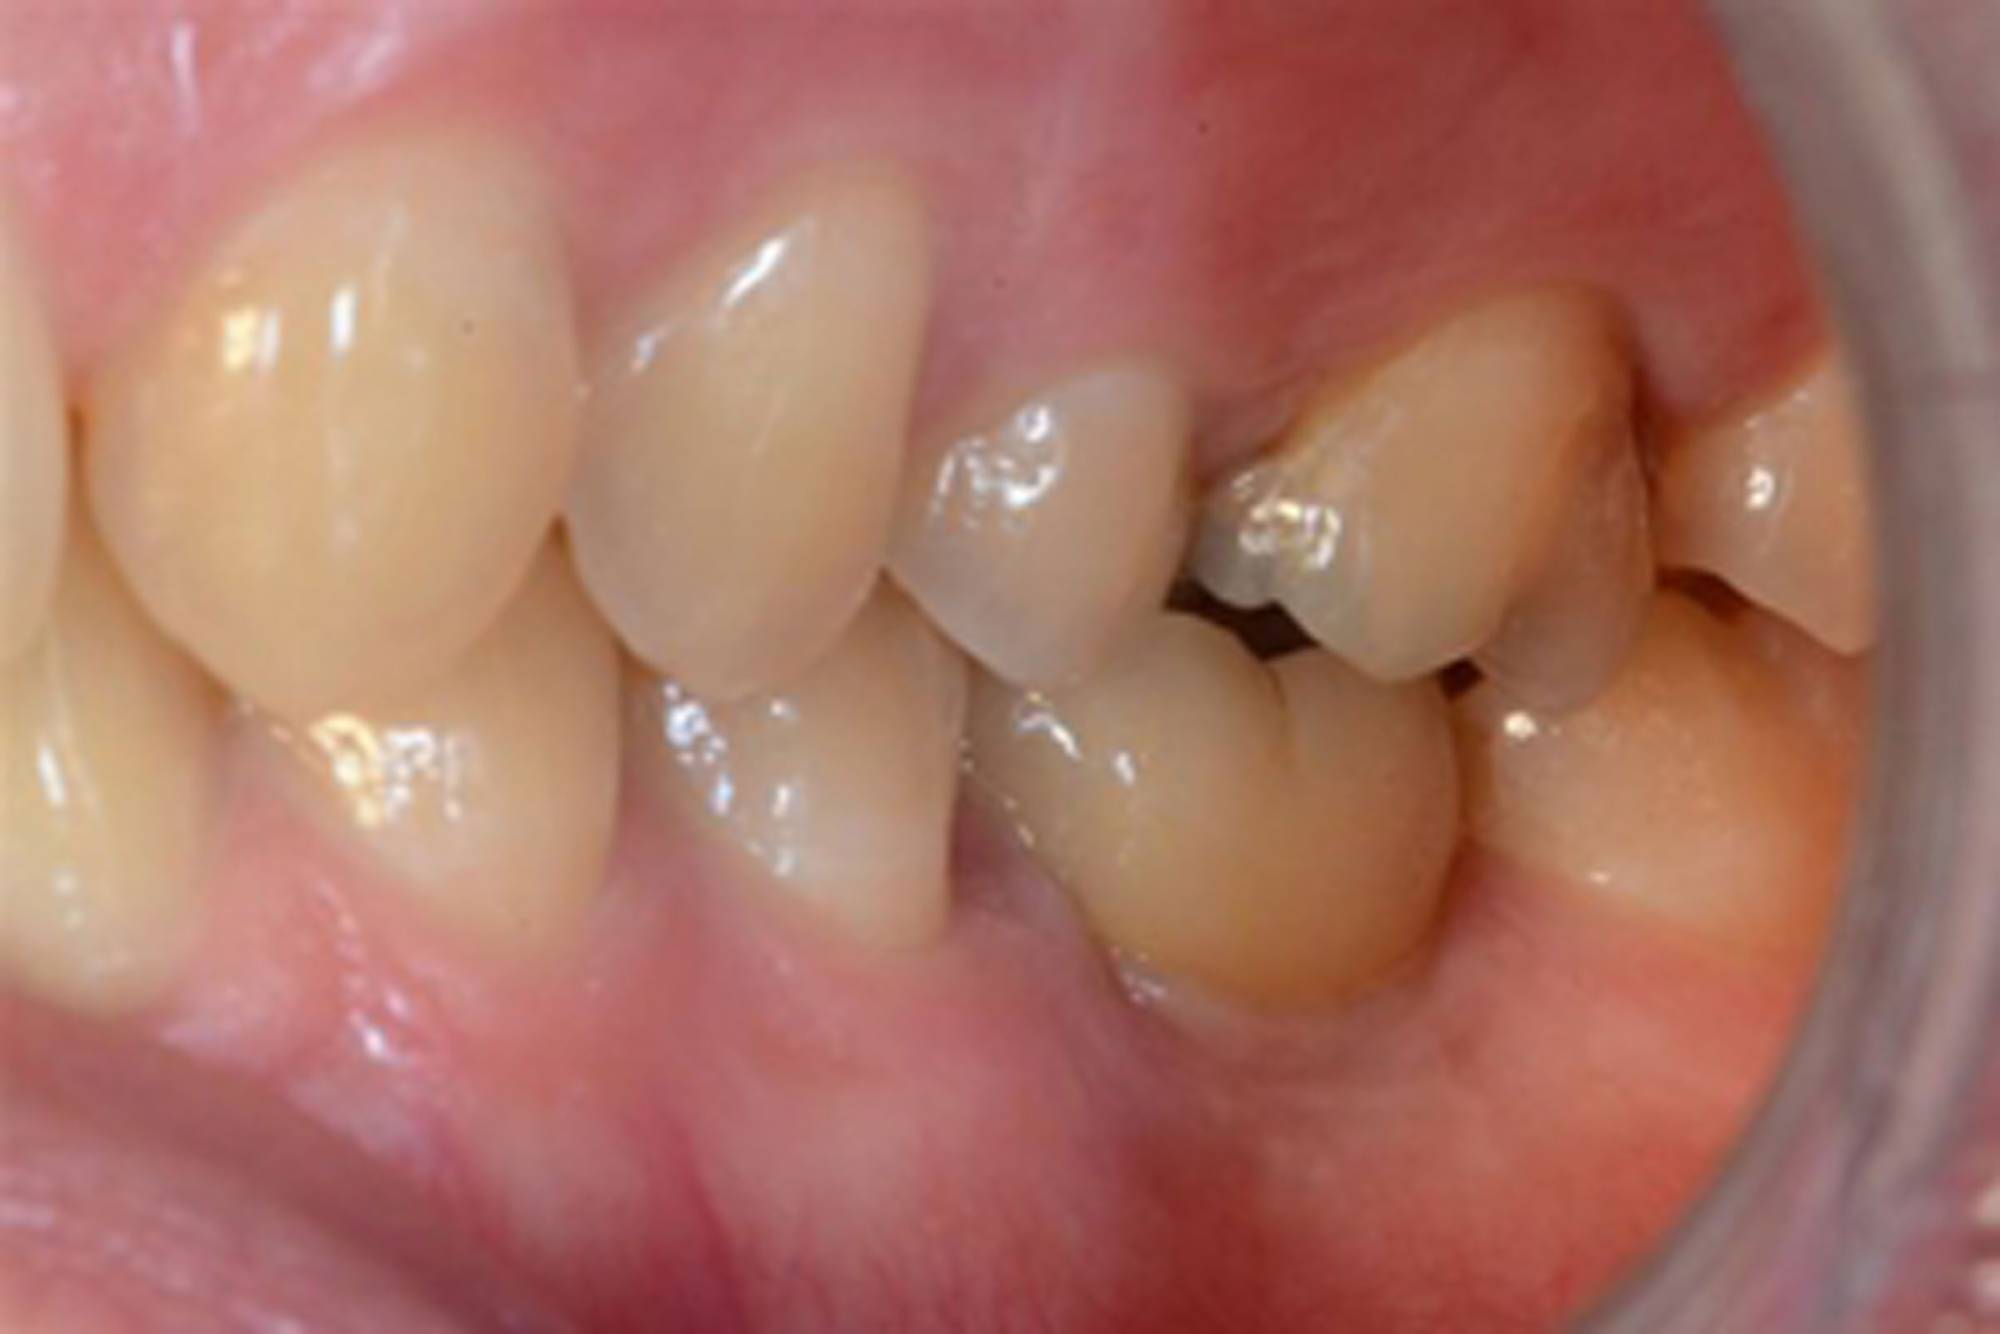

L'impianto dentale osteointegrato è una sorta di radice artificiale che si inserisce nell’osso del paziente, per rimpiazzare un dente mancante.

L'impianto, oltre a essere un metodo sicuro, garantisce l'aspetto esteriore e la piena funzionalità di un dente naturale. Oltre a ciò, mantiene l’integrità dell’osso, non va ad intaccare i denti adiacenti - come invece farebbe un ponte - e migliora l’estetica facciale prevenendo la perdita ossea.

Gli impianti sono molto versatili e possono essere usati per sostituire un dente singolo, più denti fissi o addirittura un'intera arcata. Inoltre, possono essere inseriti sotto una protesi mobile per stabilizzarla migliorandone il comfort.